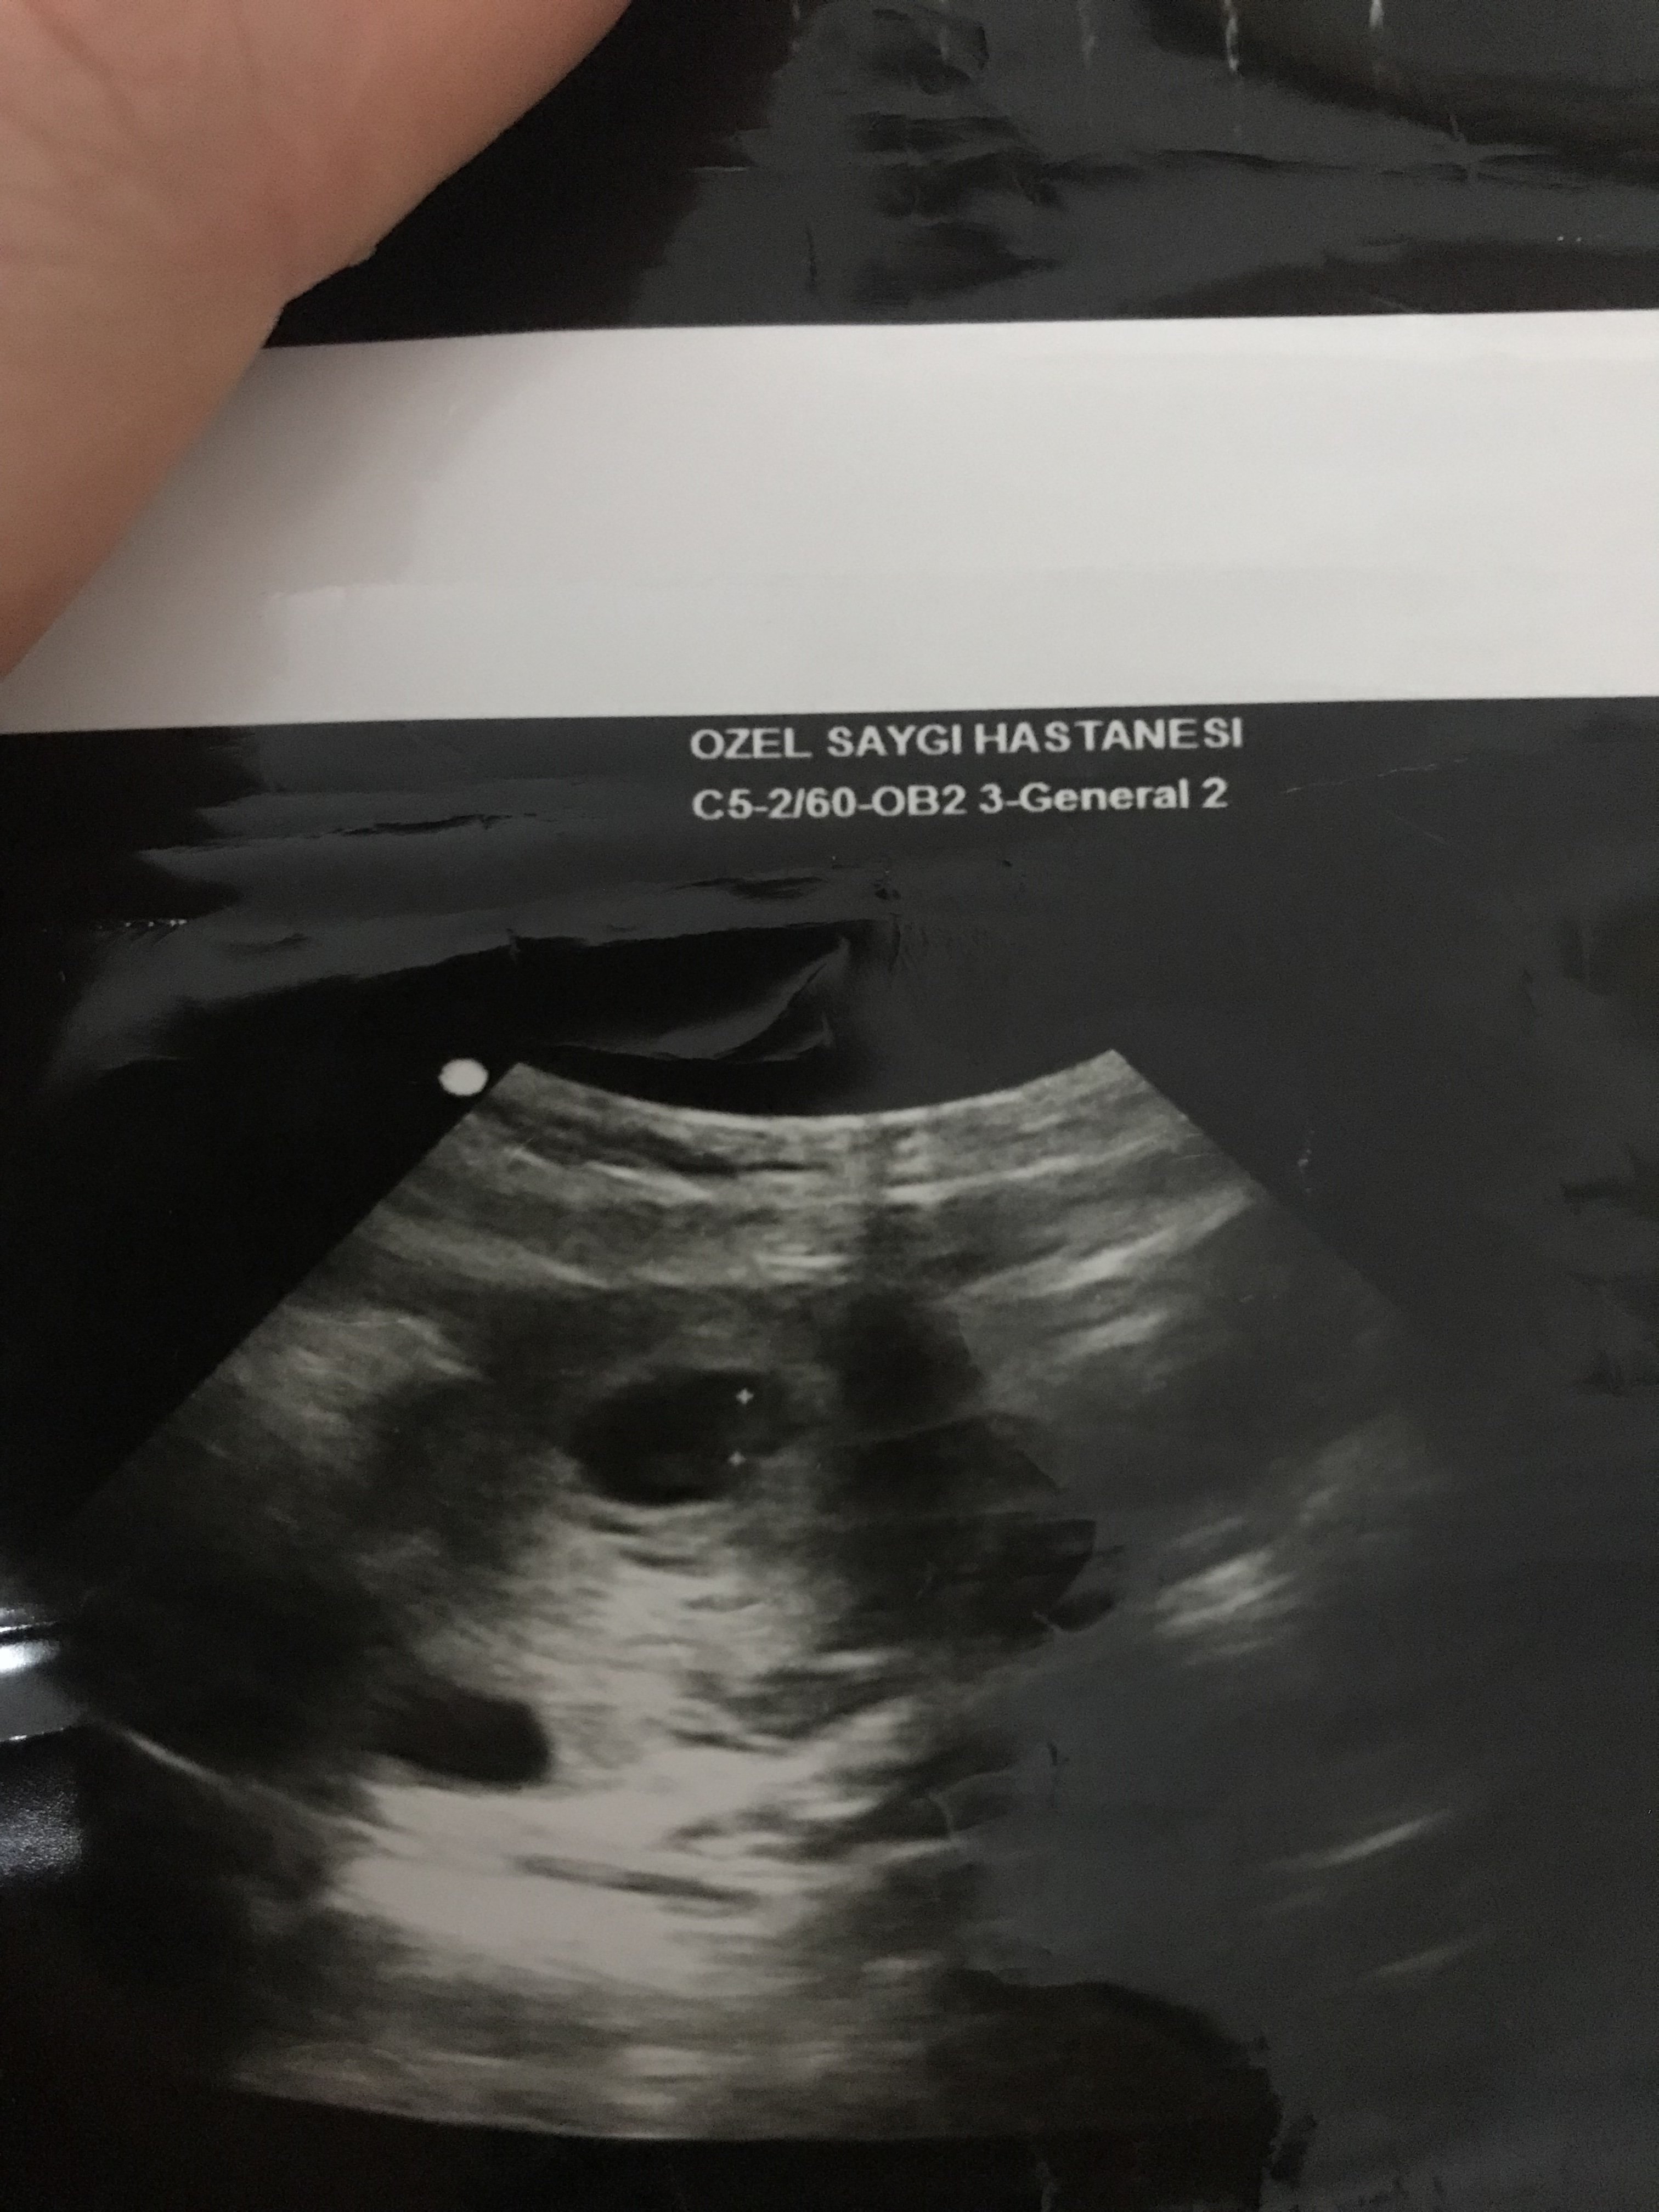

Merhaba .Bunlarda 6+4 günlük usg fotolarım.Ramzi teorisine göre de yorum yapabilir misiniz

Selamlar, bu yuvarlak kese olan bölümü yakın atar mısınız tam anlamı ile yorum yapamıyoruz görmediğimiz için